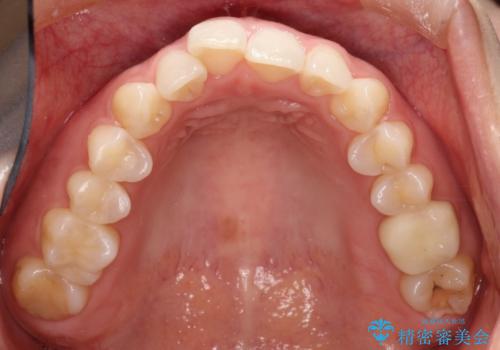

【メタルフリー】銀歯を白くしたい。オールセラミッククラウン。

- 銀歯を白くしたいと希望され来院されました。

すぐにでも白くしたいとのことで、2回目の来院で銀歯を白い仮歯に変更し喜んでいただきました。

ただ単純に白くするでけではなく拡大鏡を使用し、丁寧な処置を行なっております。